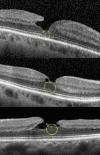

Purpose: To determine the prevalence of a central hyperreflective line in eyes with full-thickness macular holes (FTMH) and lamellar macular holes (LMH) and to elucidate the pathoanatomic importance of this optical coherence tomography (OCT) sign.

Methods: This retrospective analysis evaluated patients with FTMH and LMH at the Stein Eye Institute. Clinical data was collected and SD-OCT volume scans were analyzed for the presence of a central vertical hyperreflective line in 3 separate cohorts: patients with SD-OCT preceding FTMH development, patients with SD-OCT after pars plana vitrectomy (PPVT) treatment for FTMH, and patients with SD-OCT of LMH.

Results: In total, 93 eyes with FTMH and 88 eyes with LMH were identified. Of the 93 FTMH eyes, SD-OCT volume scans were available before development of the FTMH in 12 eyes. Of these, 6 (50%) displayed a vertical hyperreflective line preceding the development of the FTMH. Fifty-one eyes underwent PPVT with resolution of the FTMH, and 26 displayed a hyperreflective line after resolution (51%). Of the 88 eyes with LMH, 22 displayed a hyperreflective line (25%). All hyperreflective lines were noted at the central fovea.

Conclusions: SD-OCT illustrated the presence of a central vertical hyperreflective line preceding FTMH and after resolution of FTMH after PPVT in approximately one-half of cases, and concurrent with LMH in 25% of cases. This vertical hyperreflective line may represent an early SD-OCT marker for the development of FTMH, and may be a sign of central foveal dehiscence owing to disruption of the Muller cell cone.